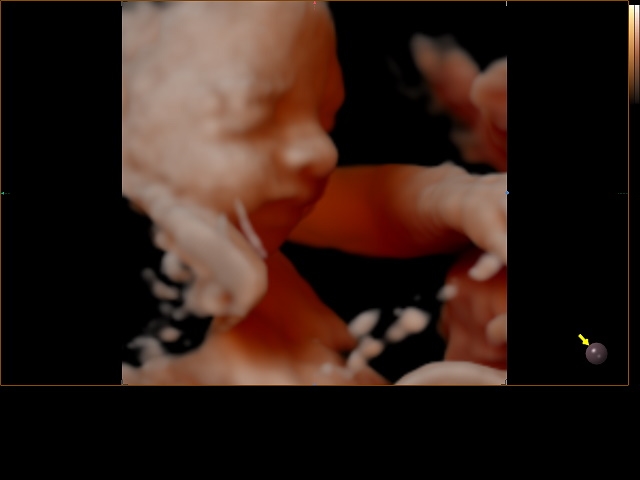

Mama en papa geven elkaar geen cadeautjes op Valentijn, maar dit jaar kozen we ervoor om deze feestdag toch een vrolijk kleurtje te geven door een extra bezoekje aan Cfor9. Je gelooft het echter misschien niet, maar jouw hoofdje was terug zo gedraaid dat we jou niet konden zien. Je staat precies even graag op de foto als jouw papa… niet dus (knipoog)!

Op 21 februari 2015 hadden we dan ook een nieuwe afspraak bij Sylvie. In plaats van jou nog eens te zien bij 32 weken zwangerschap konden we je nog even bewonderen bij 33 weken zwangerschap. Amai, wat ben je veranderd in vergelijking met de vorige keer. We zien echt dat je goed groeit. Vooral jouw bolle kaakjes vinden we zo schattig. Op het eerste zicht heb je trouwens de neus van de mama en de lipjes van de papa. Wat kijken we ernaar uit om jou te kunnen knuffelen!

Dit waren jammer genoeg wel de laatste 3D-beelden die we zullen kunnen zien van jou tijdens de zwangerschap. In het ziekenhuis maken ze enkel een 2D-echo en omdat je meer en meer met jouw hoofdje in mama’s bekken daalt zal Sylvie geen foto’s meer van jou kunnen maken.